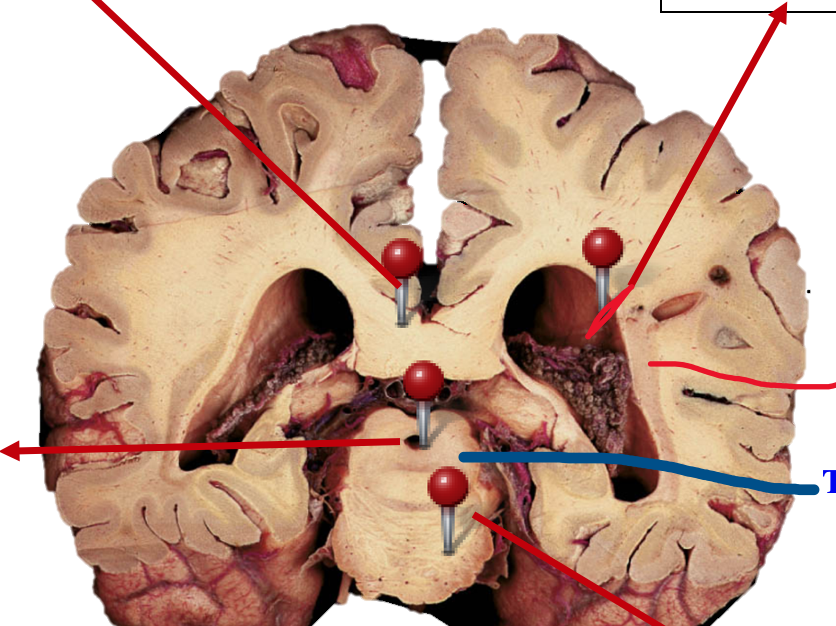

What is the caudate nuceli?

Collection of neuronal cell bodies within the cerebral hemisphere

Label the ventricles of the brain & the parts of the basal glanglia